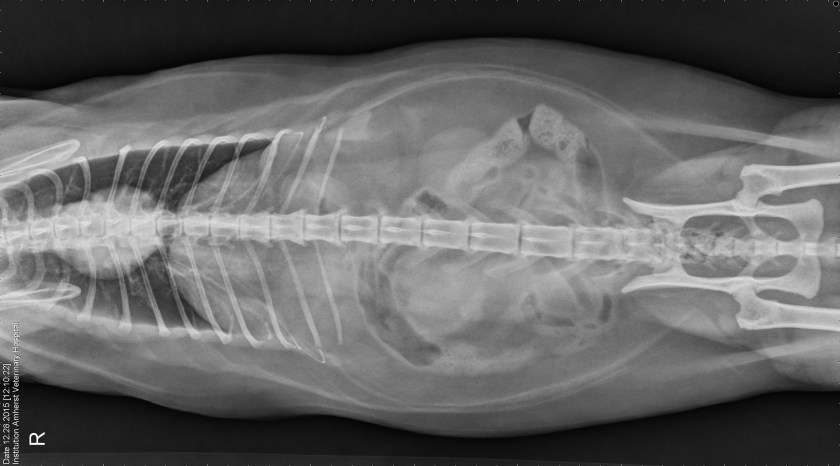

Here she is. In all her radiograph splendour.  Fuius Schmeezer Exarchas.  Cat Pictures    “Radiograph”. I wondered about that. Still just an “X-Ray”. Nothin to see here.

Radiograph Amherst Veteranary

Fuius Radiograph Amherst Veterinary

It’s the first time I’ve ever seen the Islets of Langerhans and where exactly they are.  I mean, we’ve always known of the Isles.  But where exactly were they?  Are they?  Biology.  Couldn’t get excited.  So this is new.  To ignore this now would be a mistake of epic proportions.